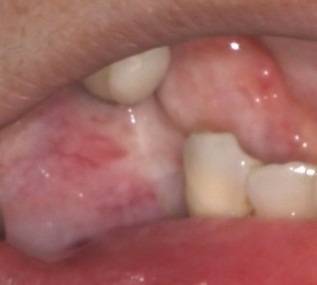

術中

インプラント埋入手術では、局所麻酔・歯肉の切開・インプラント床の形成・埋入・縫合などを行いますがこれは一連の流れであり、途中でやめることはあまりありません。

従って、インプラント埋入手術日は体調を整えてもらい、場合によっては日程を変更することもあります。

ただし、多くの場合で局所麻酔下で行いますので適宜休息を取りながら、患者さんと状況を確認しながら進めることができます。